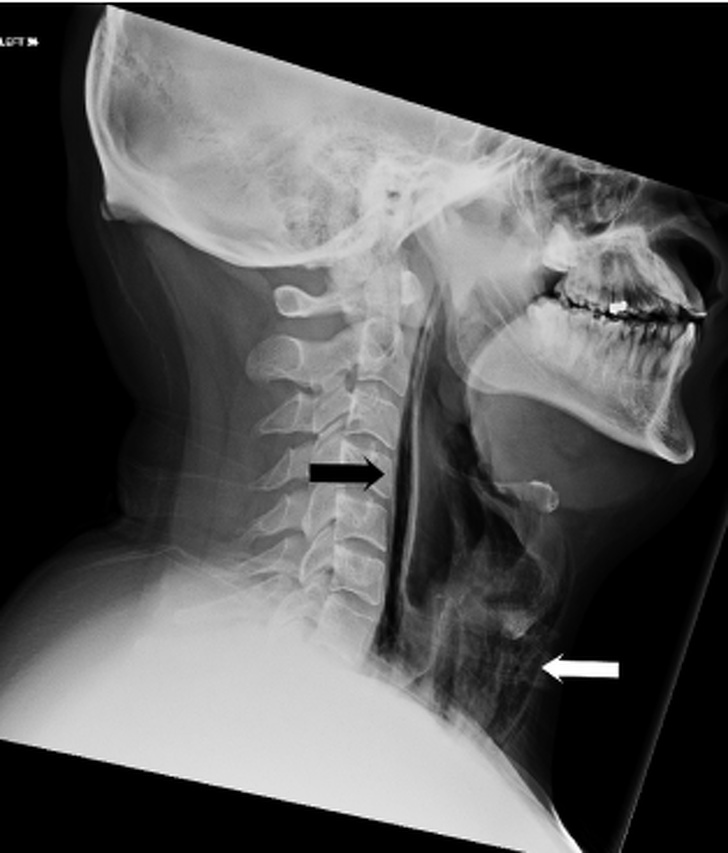

Человек попробовал чихнуть, закрыв нос и рот. Из-за этого у него образовалась дыра в глотке